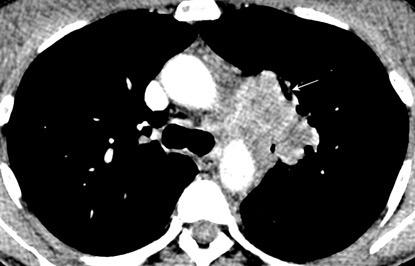

Hemorragia mediastínica

Hematoma intramural aórtico

Quiste broncogénico (a veces)

Post- linfografía

Hematoma mediastínico post-cirugía aórtica con alta densidad y derrames pleurales (densidad baja)

Mod. de Glazer HS et al. High-attenuation mediastinal masses on unenhanced CT. Radiology 1991